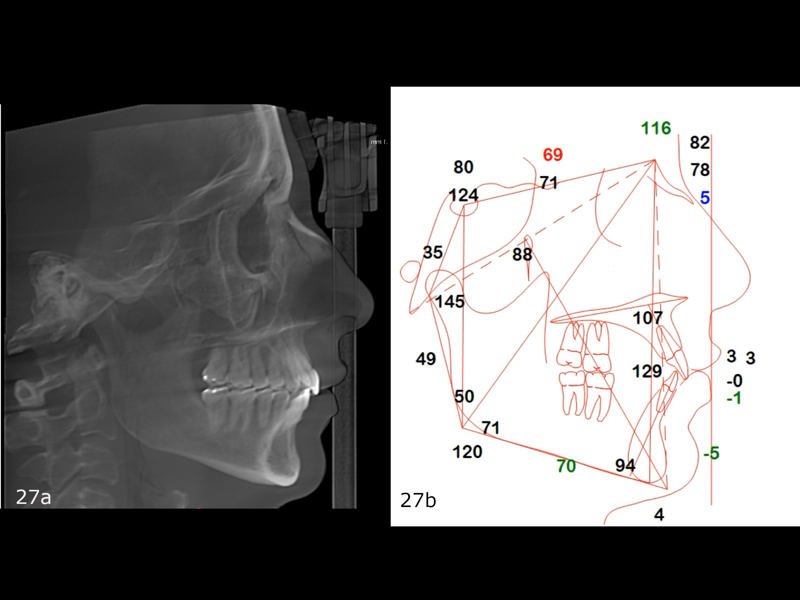

The final dental panoramic tomogram showed the correct levelling of the occlusal planes and root positions (Fig. 26). The final cephalometric tracing showed closure of the facial angle thanks to the posterior intrusion and mandibular auto-rotation (Figs. 27 & 28). Mandibular antero-rotation shortens the lower facial third, improving lip competence and ultimately the facial profile. The CBCT images of the TMJs showed the correct position of the condyles within the glenoid fossae (Fig. 29). When looking at the airway on the CBCT scan, we also saw an improvement of the patient’s airway (Fig. 30).